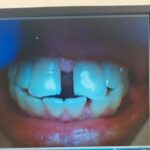

Photos